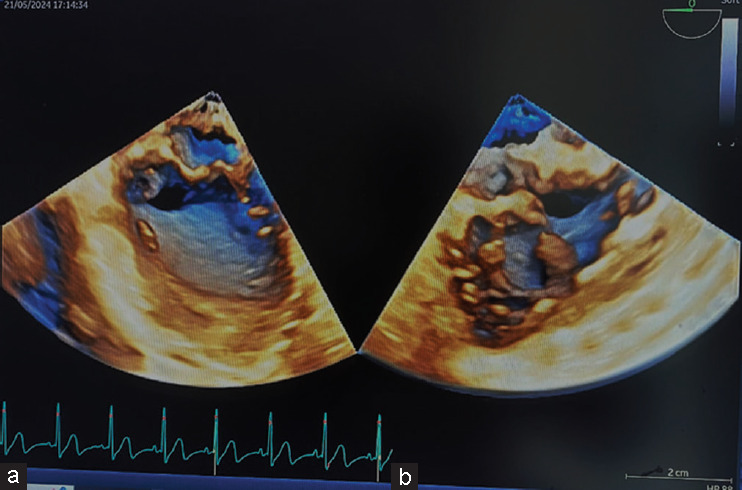

Methods: Recent advancements in the field of miniaturization have led to the development of a new pediatric 3D TEE probe, specifically designed for young children (weight ≥4.5 kg). This probe features a smaller, flexible design and high-spatial and temporal resolution, enabling detailed views of intracardiac structures and real-time imaging crucial for complex diagnosis, planning interventional and surgical procedures. We used this new probe in pediatric cases (weight between 4.5 and 6 kg) with complex congenital heart disease.

Results: In double-outlet right ventricle or in Taussig Bing anomaly the new 3D TEE probe enabled detailed assessment of ventricular septal defect and its relations with tricuspid valve apparatus, and provided details of mitral valve leaflets not detectable by the transthoracic approach, even in small children.

Conclusions: These cases highlight the probe's ability to provide detailed anatomical information, enhancing surgical planning and outcomes. The pediatric 3D TEE probe has the potential to be a game changer in defining intracardiac anatomy in complex CHD.